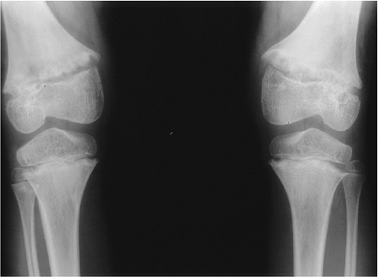

Key Facts

Epiphyseal dysplasias have two broad categories:

Spondyloepiphyseal dysplasia: platyspondyly and beaking of the vertebra

Multiple epiphyseal dysplasia: minimal or no spine abnormalities

Multiple epiphyseal dysplasia may present in the tarda (childhood) or congenital (first year of life) forms.

Multiple epiphyseal dysplasia tarda:

Both sexes equally affected

Bilateral symmetric involvement of hips, knees, ankles, shoulders, and wrists

No mental retardation

Present in early childhood with joint pain and gait disturbances

Early degenerative joint disease

Radiographic features:

Long bone epiphysis appears late

Irregular and fragmented when ossified

Slipped epiphysis, coxa vara, and joint deformities common

FIGURE 15-20 Multiple epiphyseal dysplasia. Radiographs of the hip (A), left knee (B,C), left foot and ankle (D,E), and left wrist (F) show lack of epiphyseal ossification centers with punctate calcifications in the knee.